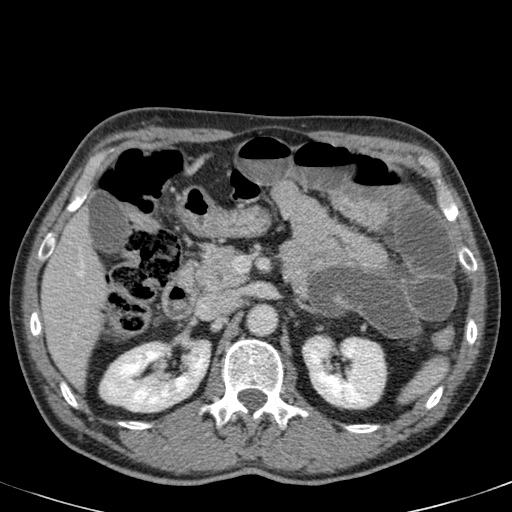

Đây là một bệnh nhân bị tắc ruột non.

Cuộn qua các hình ảnh.

Bạn có thể tìm thấy quai kín và nguyên nhân gây ra nó không?

Tắc ruột dạng quai kín với các quai ruột giãn xếp theo hình nan hoa. Có dày thành ruột và phù nề mạc treo gợi ý thiếu máu cục bộ

Một hình ảnh quan trọng khác của tắc ruột dạng quai kín là các quai ruột non giãn xếp theo hình nan hoa với các mạch máu mạc treo hội tụ về một điểm trung tâm.

Các dấu hiệu thiếu máu cục bộ trong tắc ruột dạng quai kín tương tự như ở bệnh nhân thiếu máu mạc treo do các nguyên nhân khác:

- dày thành ruột

- phù nề mạc treo

- cổ trướng

- sự ngấm thuốc của thành ruột trong thiếu máu cục bộ có thể bình thường, tăng hoặc giảm.